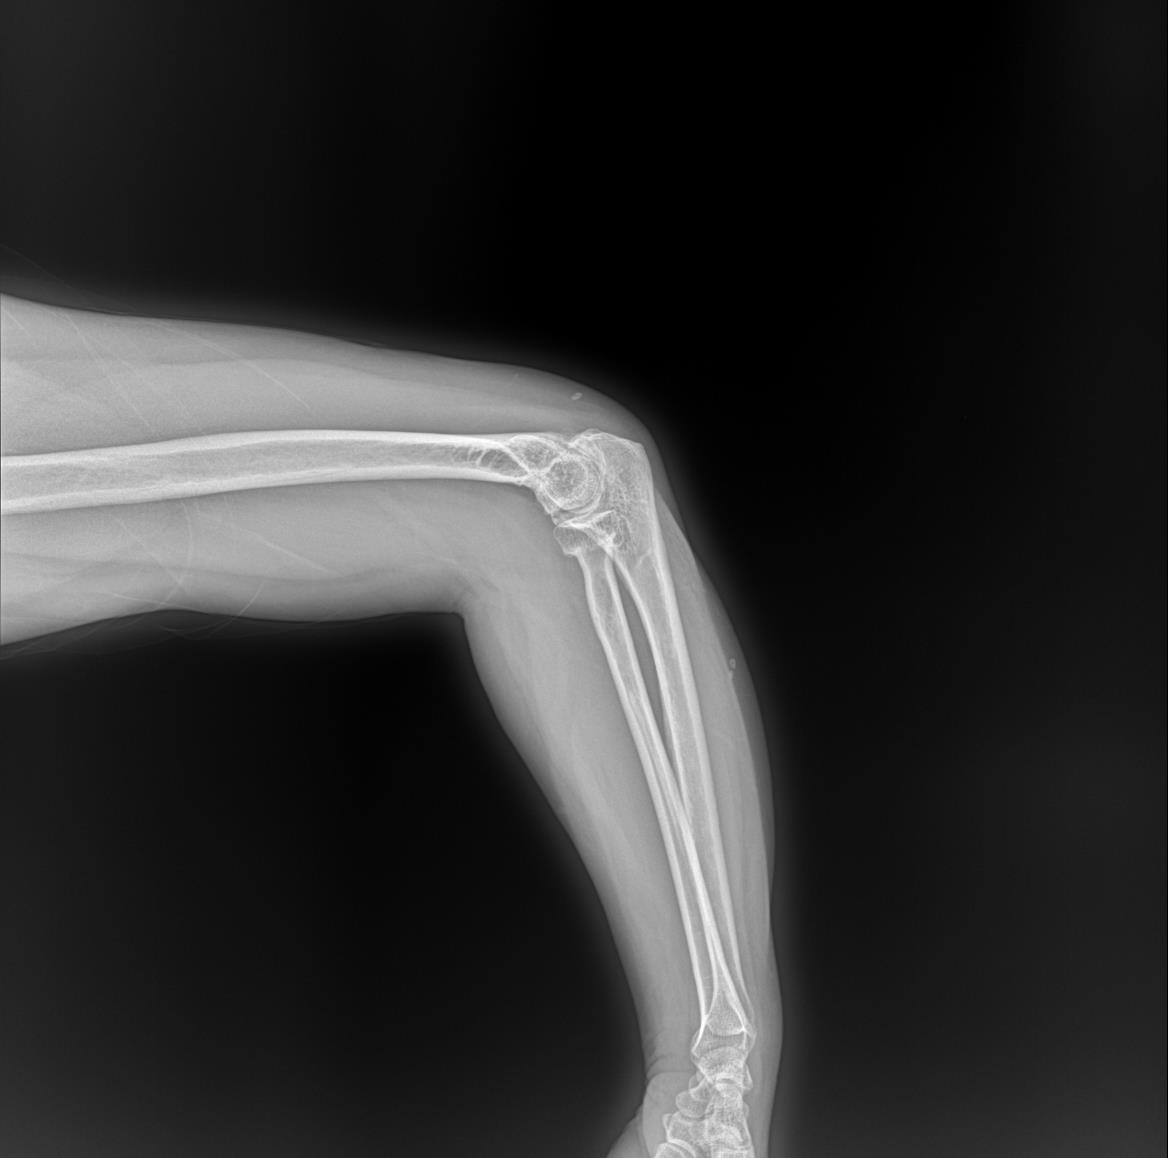

左肘关节外伤就诊